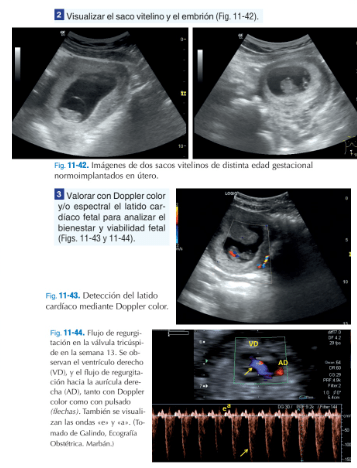

"ECOmécum, la herramienta fundamental para saber deecografía clínica." Con la llegada de los ecógrafos a los servicios de urgencia y atención primaria,resulta imprescindible formarseen su utilización yECOmécumserá la forma de conseguirlo. Orientado para la resolución de cualquier situación comprometida o duda en el diagnóstico ecográfico, este práctico manual, aporta lainformación necesaria en la clínica diaria; centrado especialmente en laecografía abdominal. Con un método sencillo y muy práctico, empieza por la base más fundamental y por unesquema de exploracióncon los cortes necesarios, posición del transductor, elresultado de la imagen ecográfica y la interpretación de la patologíahallada. Sin duda, una fórmula muy efectiva y rápida para el profesional, ya sea joven con poca experiencia o experto con necesidades de actualización en las nuevas técnicas.